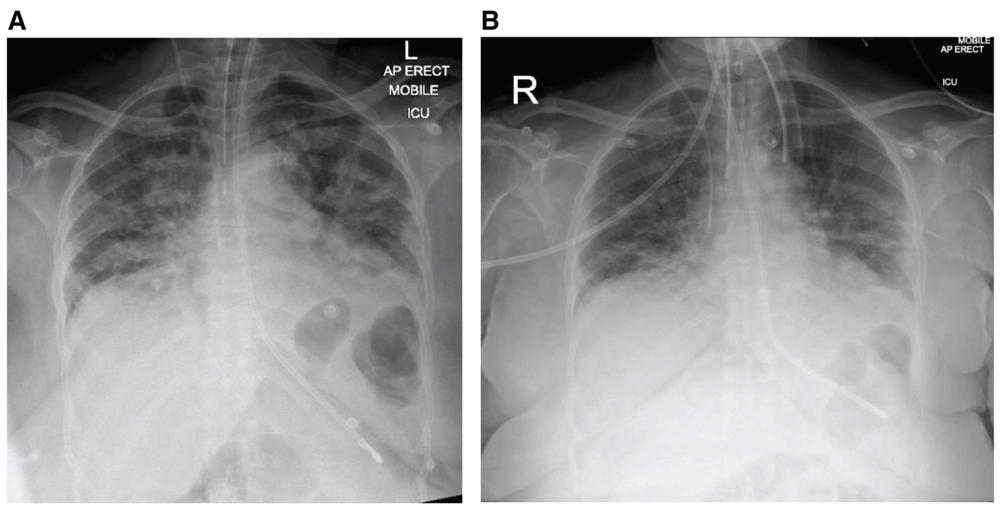

A 69-year-old female, non-smoker with a background history of hypertension (controlled by amlodipine 5 mg once daily) presented to the emergency department with a three-day history of pyrexia and tachycardia. Admission chest X-ray (CXR) showed bilateral pulmonary infiltrates. On day 5 after onset of symptoms, she was transferred to the intensive care unit where she required tracheal intubation and invasive ventilation for worsening type 1 respiratory failure. An 8-mm external diameter endotracheal tube (ETT, Portex, Hythe, UK) was sited on first attempt with video-laryngoscopy, secured at 22 cm at the lips, with tip position subsequently confirmed on CXR (Figure 1A)4. Laryngoscopy view was grade 15, and no pathology was recorded.

(A) Post-intubation plain chest radiograph, on ICU on day 5 post-onset of symptoms. (B) Plain chest radiograph on day 10 post-onset of symptoms.

With reducing levels of ventilatory support requirement (spontaneous effort, FiO2 0.3, pressure support (PS) 5 cm H2O, positive end expiratory pressure (PEEP) 5 cm H2O, extubation was attempted five days later (day 10), but was unsuccessful due to excessive resistance to egress of the ETT. When repeat video-laryngoscopy suggested laryngeal oedema, 6.6 mg three times daily dexamethasone was commenced. Repeat CXR demonstrated no causative pathology (Figure 1B). Two further attempts at extubation over successive days again failed, characterised by lack of audible leak after cuff deflation and almost complete immobility of the tube on reasonable traction.